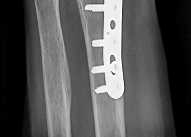

Question 18:

A 35-year-old farmer sustains an open midshaft tibia fracture when a tractor rolls over his leg. The wound is 12 cm long with significant contamination, including soil and manure. According to standard orthopedic trauma guidelines, what is the most appropriate prophylactic intravenous antibiotic regimen?

Correct Answer: First-generation cephalosporin, an aminoglycoside, and high-dose penicillin

Explanation:

This is a Gustilo-Anderson Type III open fracture occurring in a farming environment. The standard antibiotic protocol for a Type III open fracture includes a first-generation cephalosporin (for Gram-positive coverage) and an aminoglycoside (for Gram-negative coverage). However, when the wound is heavily contaminated with soil, manure, or standing water (e.g., farm injuries), the addition of high-dose penicillin is indicated to provide coverage against anaerobic organisms, particularly Clostridium species, to prevent gas gangrene.